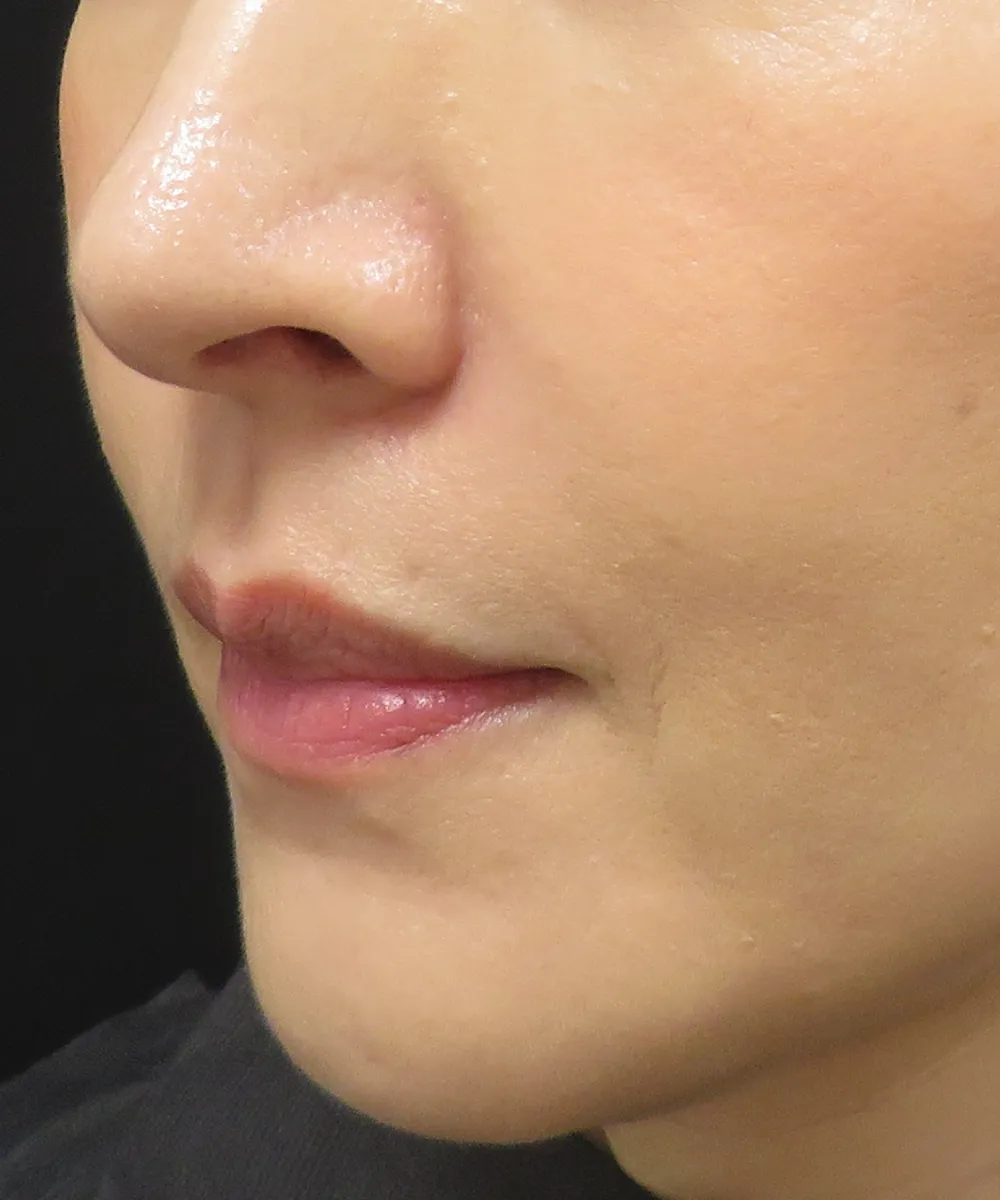

PRP注射の症例写真

PRP注射とpスリム注射の併用例